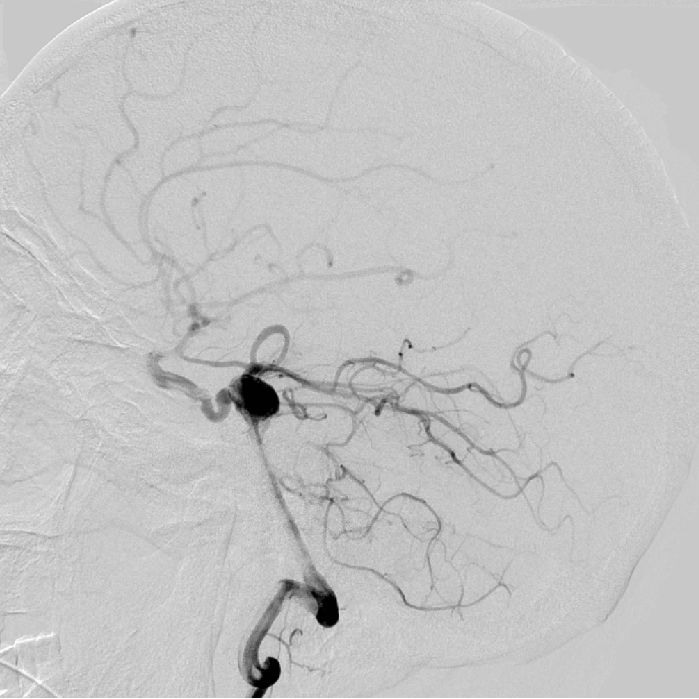

新医神外双周刊第二期一例原始三叉动脉伴动脉瘤病例分享

为什么又出现这张照片呢?因为这里有原始三叉动脉,可遇不可求呀!

原始三叉动脉

永存三叉动脉